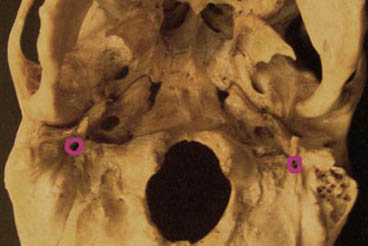

The facial nerve is primarily a motor nerve, but also carries special sensory (taste) fibers. CN VII emerges between the pons and medulla on the brain and exits the skull through the internal acoustic meatus, facial canal and finally the STYLOMASTOID FORAMEN. Branches of the facial nerve supply the MUSCLES OF FACIAL EXPRESSION, taste to the anterior two thirds of the tongue (chorda tympani), parasympathetic innervation to the submandibular and sublingual glands (chorda tympani), and the lacrimal glands and mucous glands of the soft palate, nose, and paranasal sinuses (greater petrosal nerve).